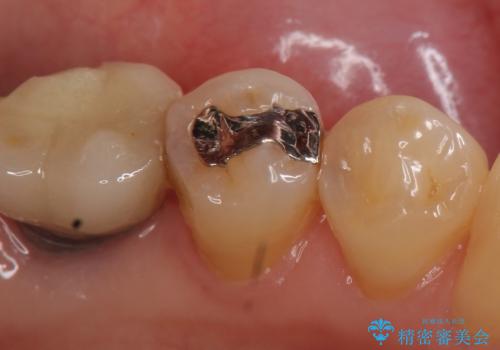

- 左下5番目の銀歯が気になるのでセラミックにしたいといらっしゃった方の症例です。

銀歯及び虫歯を除去後、セラミックインレーによる修復を行いました。